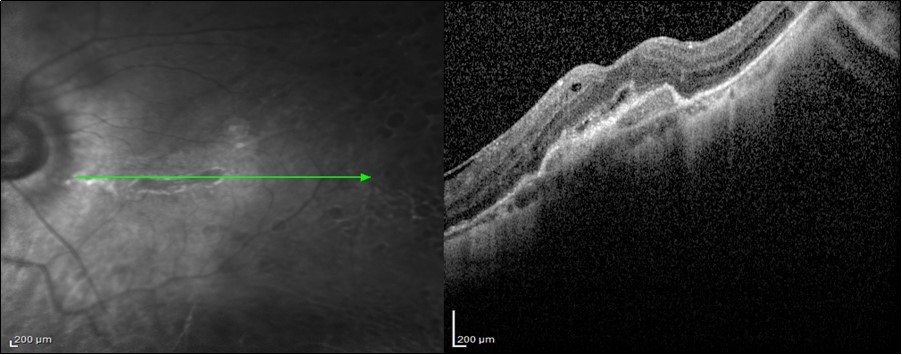

Figure 1.4 years Post-SOR SD-OCT image of a 42-year-old patient with BCVA 6/12 after anatomical repair of a macula-on GRT with PPV + SOI with preoperative BCVA 6/18. We can, notice the presence ERM and CME.

4 years Post-SOR SD-OCT image of a 42-year-old patient with BCVA 6/12 after anatomical repair of a macula-on GRT with PPV + SOI with preoperative BCVA 6/18. We can, notice the presence ERM and CME.